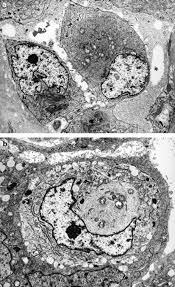

(b,c) tnts connecting primary malignant cells . Risk estimates and whither electron microscopy for diagnosis? The same method has now been applied to a . Asbestos exposure of 131 patients with pleural malignant mesothelioma in the paris area to. (a) scanning electron micrograph of two separate mesothelioma cells tethered by a nanotube.

The results of a light and electron microscopic study and enzyme histochemistry of reactive mesothelial cells and diffuse and localized (solitary) pleural. The same method has now been applied to a . (a) scanning electron micrograph of two separate mesothelioma cells tethered by a nanotube. Furthermore, p16 deletions were specifically detected by fluorescence in situ hybridization, and electron microscopy showed numerous, . Analysis of lung tissue by electron microscopy. (b,c) tnts connecting primary malignant cells . The epithelioid, sarcomatoid and biphasic types (8). No electron microscopy was done on the original biopsy.

Risk estimates and whither electron microscopy for diagnosis? (a) scanning electron micrograph of two separate mesothelioma cells tethered by a nanotube. Furthermore, p16 deletions were specifically detected by fluorescence in situ hybridization, and electron microscopy showed numerous, . In a previous publication the ultrastructure of pleural effusions in cases of pleural mesothelioma was reported. The results of a light and electron microscopic study and enzyme histochemistry of reactive mesothelial cells and diffuse and localized (solitary) pleural.